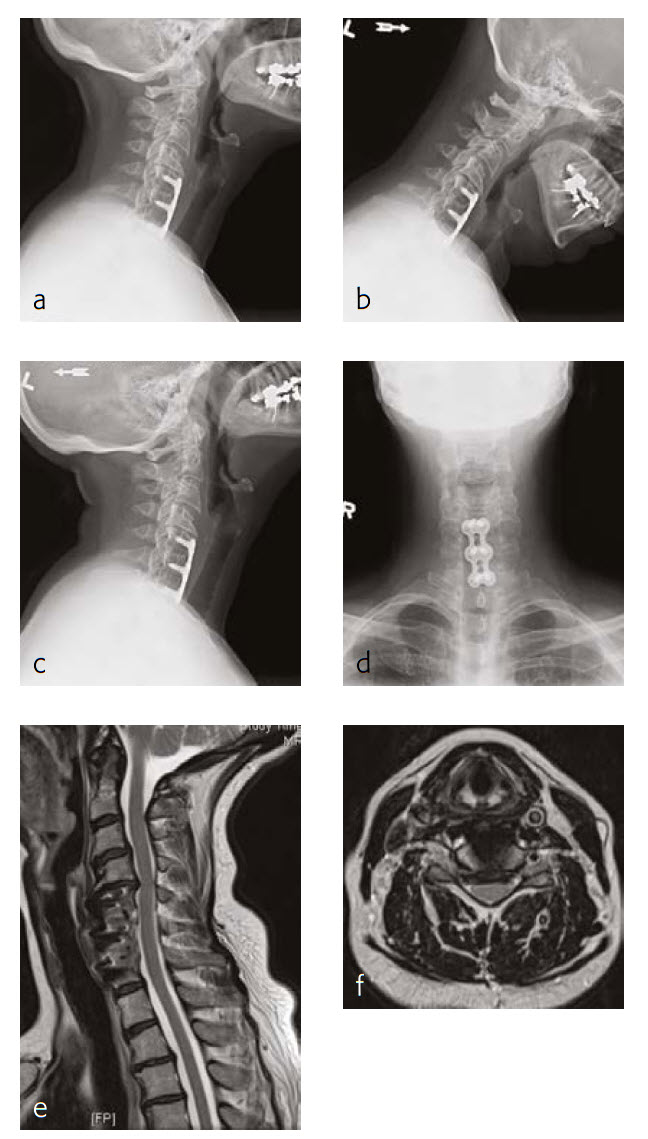

Case 3: A 46-year-old woman with neck pain and upper extremity paresthesia

A 46-year-old woman presented with one-year history of neck pain, upper extremity paresthesia, weakness, and subjective numbness (Fig 5). Her right upper extremity was worse than her left, with loss of function and debilitating pain. She described cramping in her upper extremities without etiology and without alleviating factors.

She had not been responsive to anti-inflammatory medications nor other nonoperative treatment including physical therapy. She had trouble with many of her activities of daily living due to breaks that must be taken due to her pain, as well as the inability to do certain things like open jars due to weakness.

Musculoskeletally, she had no obvious deformity in any of her extremities. Her bilateral upper extremities had strength testing of 5/5 in shoulder abduction, elbow flexion/extension, wrist extension/flexion, and finger abduction/flexion. Bilateral lower extremities showed 5/5 strength with hip flexion bilaterally, as well as bilateral 5/5 strength knee extension, dorsiflexion, plantar flexion of the ankle, and firing EHL.

She had sensation that is intact in all dermatomes. She had no pathological reflexes and no clonus. There was normal tandem gait.

Review of the patients outside imaging showed congenital stenosis of the cervical spine, as well as multilevel disk disease and concomitant acquired stenosis in the foramen of C4-C5, C5-C6, and C6-C7 where it was at its most significant level.

Follow-up (4 months)

At the 4-month follow-up, the patients symptoms were largely resolved and she has been able to return to work (Fig 6). She was very satisfied with her outcome. made significant progress in terms of his left upper extremity range-of-motion and strength.